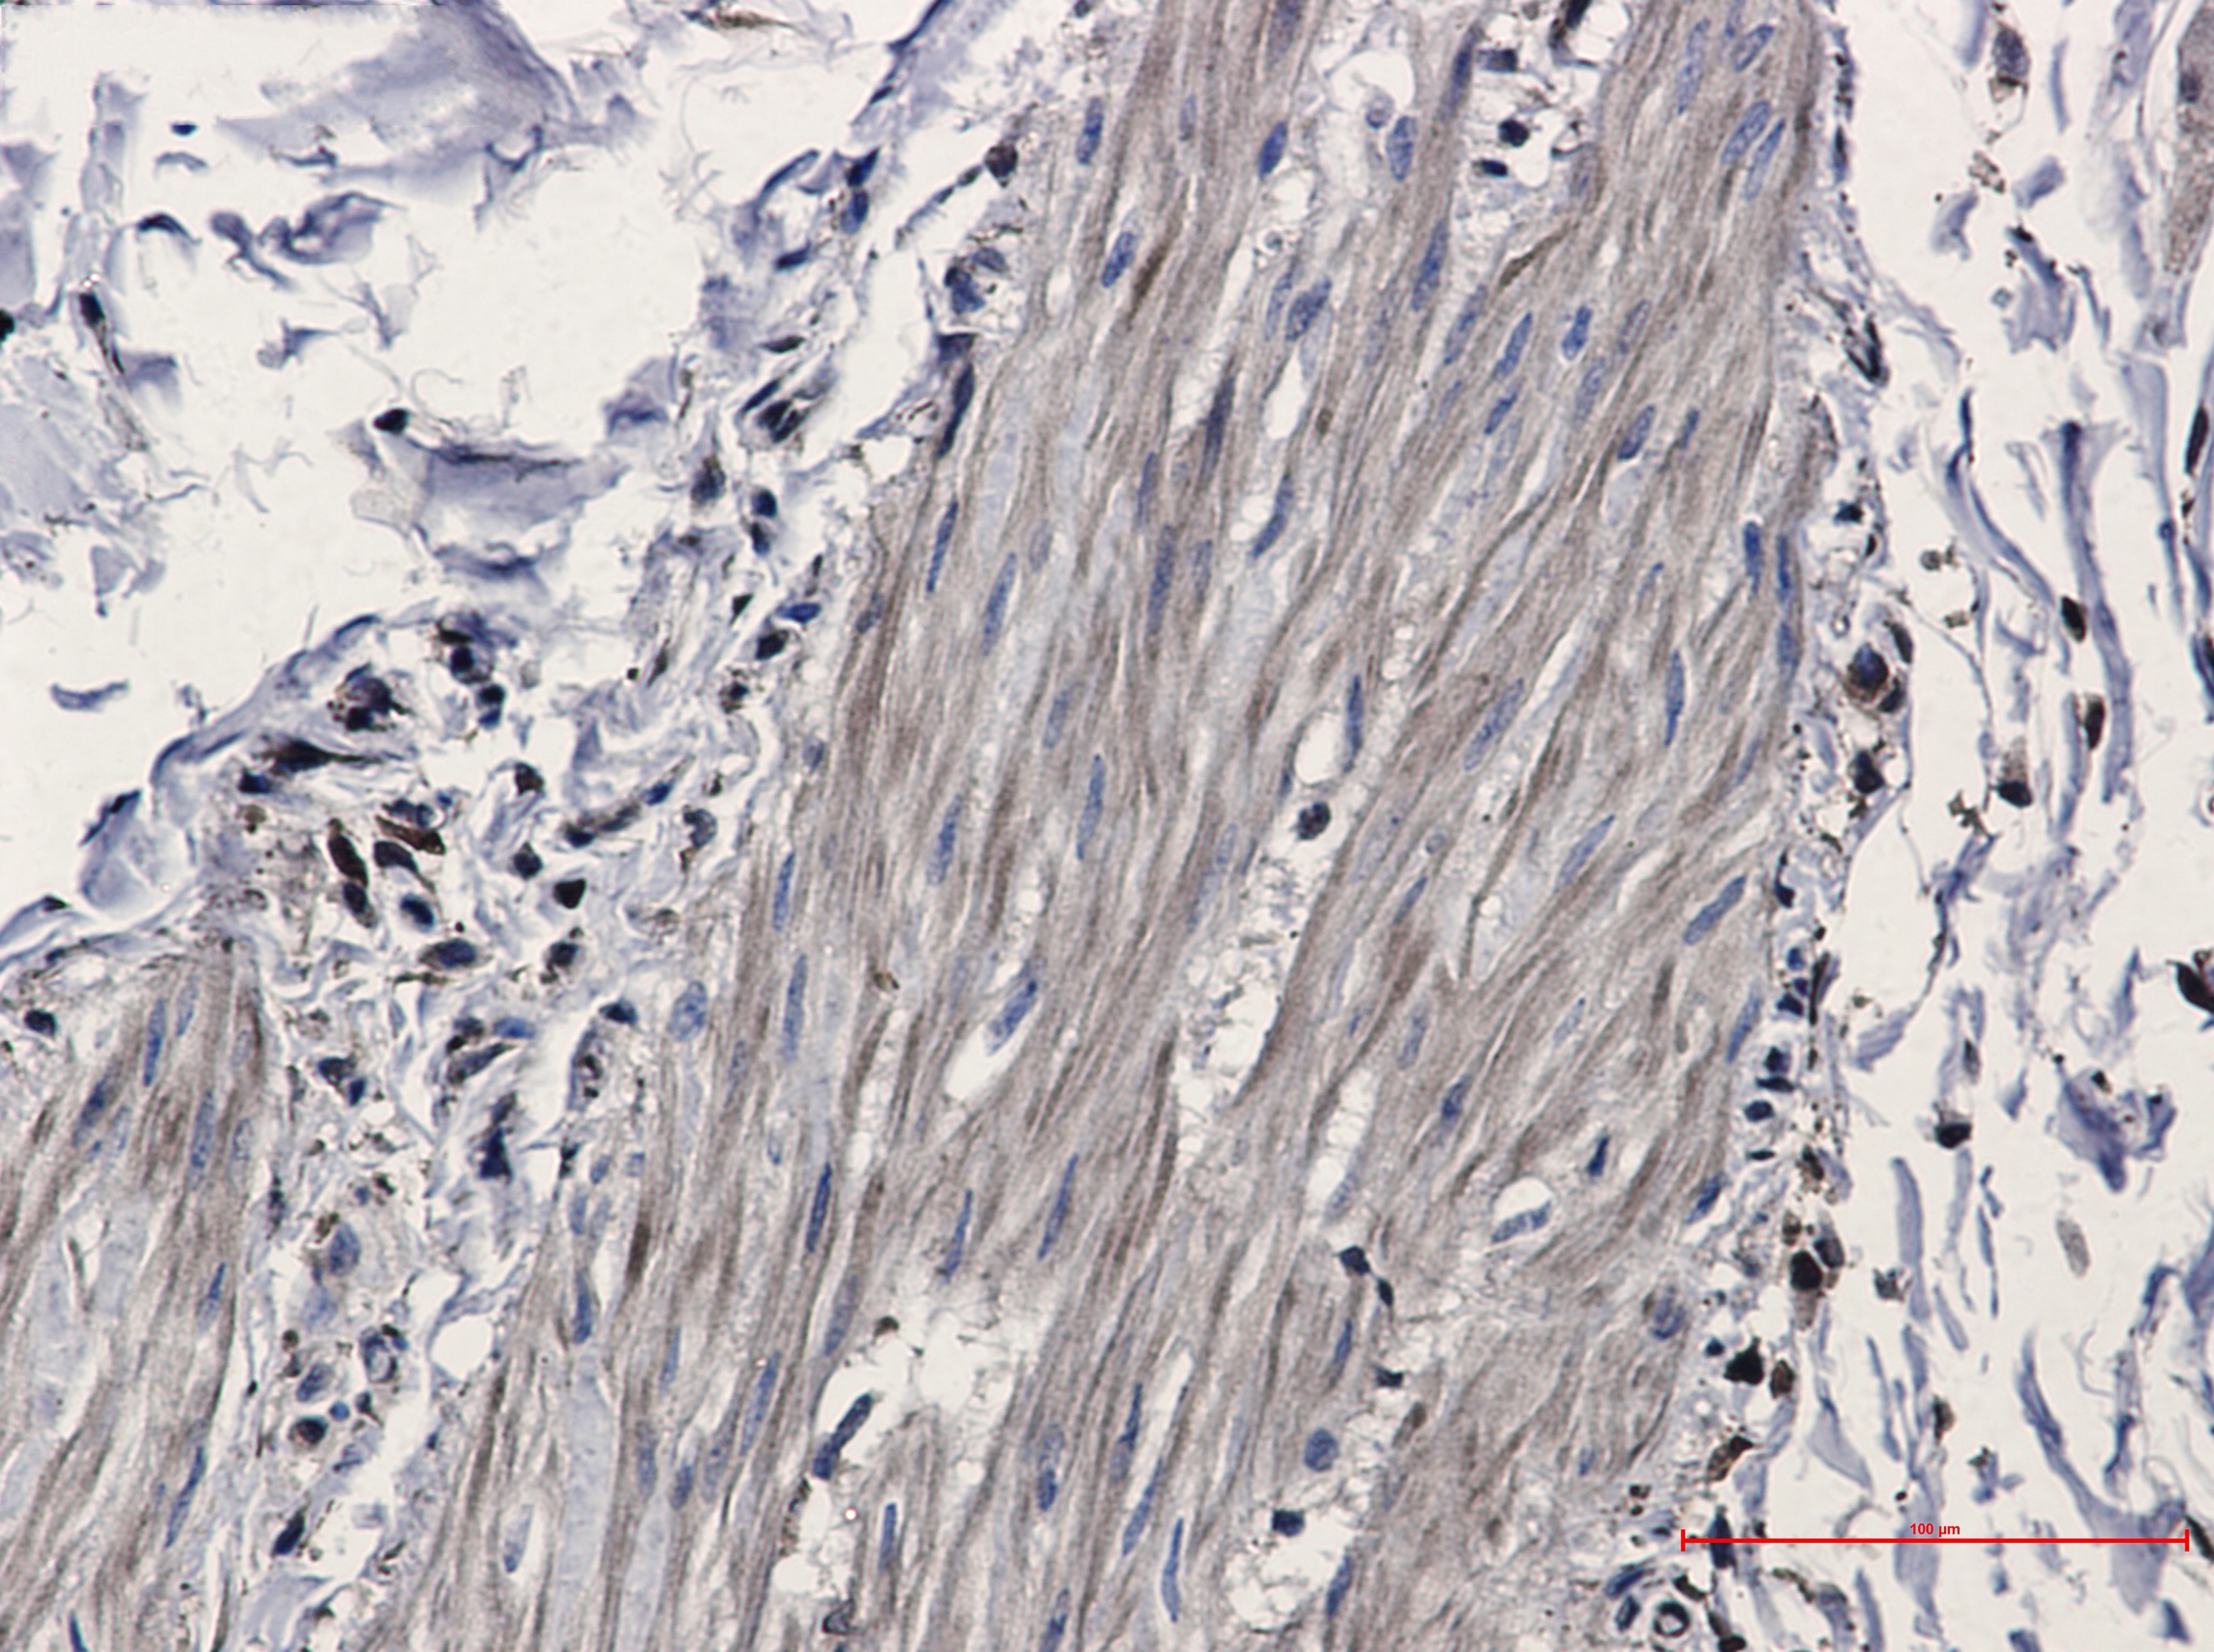

Immunohistochemistry of Isocitrate dehydrogenase in paraffin-embedded Human Cholangiocarcinoma using Isocitrate dehydrogenase Rabbit mAb at dilution 1/20